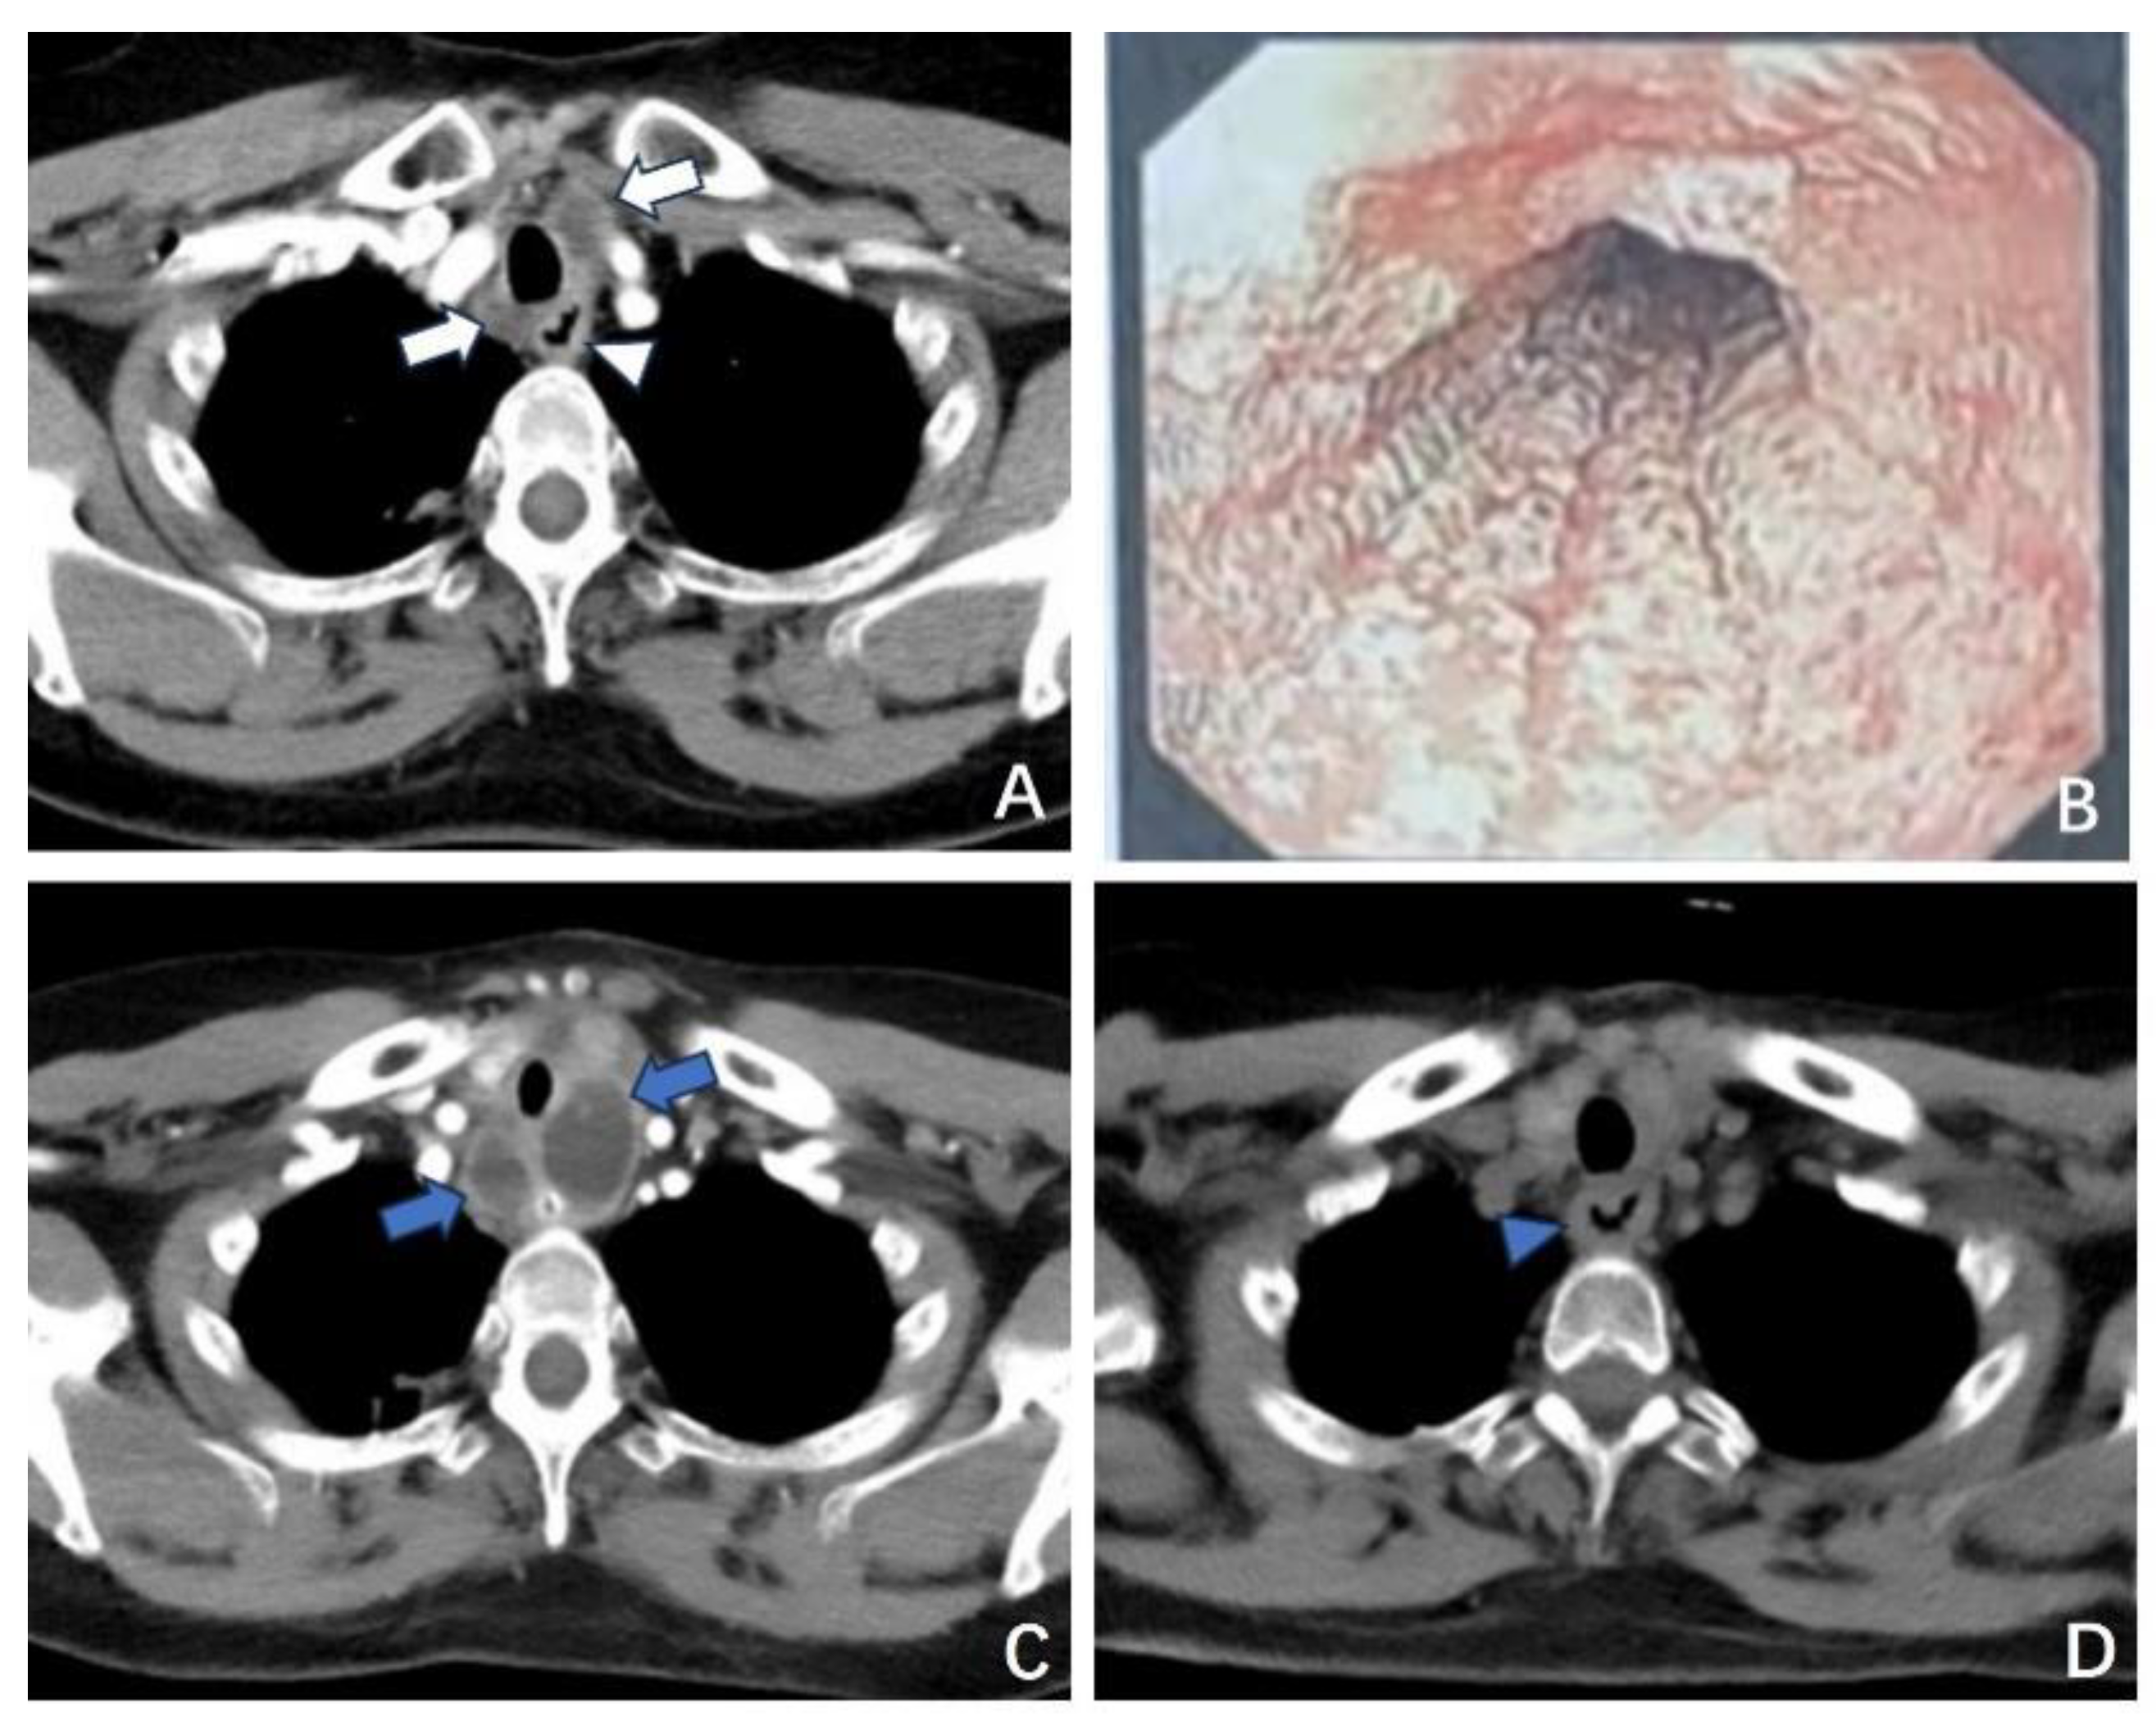

3.1.2. Case 2